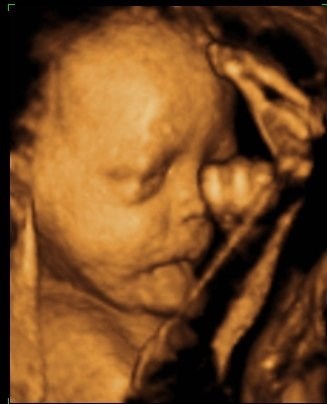

Søger man på Google kommer der kun 3D-billeder.

Så jeg vil høre om nogen herinde har et billede eller to fra uge 28 de vil vise? Og hvor lang var jeres baby, og fik I vægt at vide?